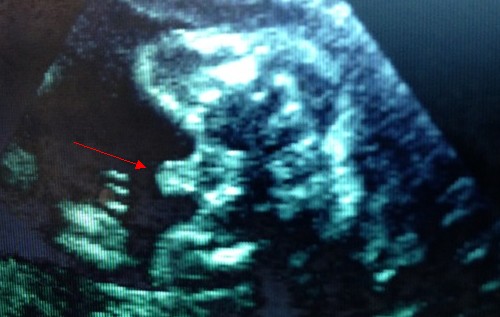

23周男寶B超圖,小jj辣么明顯。